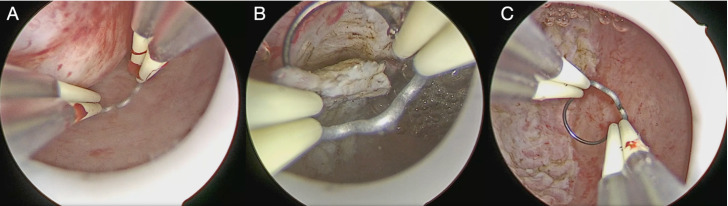

Abstract Image